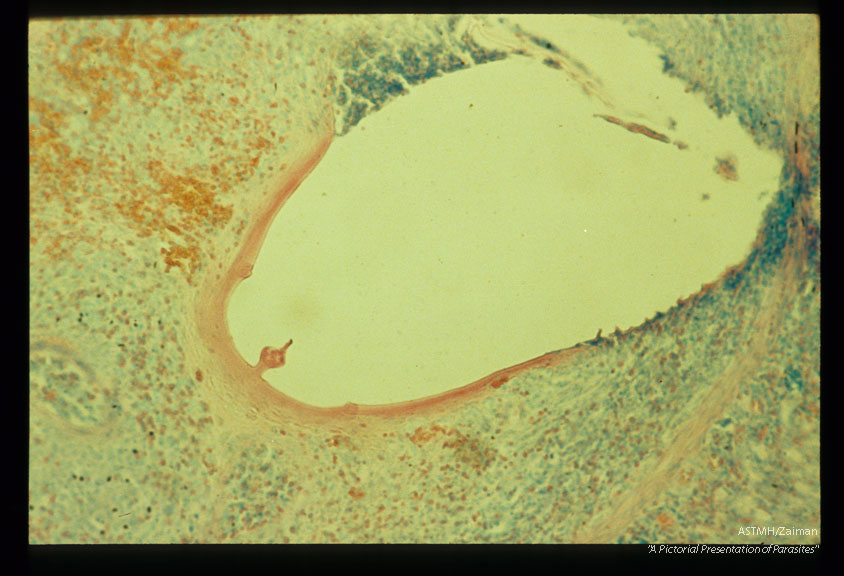

Evacuated attachment cap in the submucosa of an experimentally infected guinea pig.

Description: Evacuated attachment cap in the submucosa of an experimentally infected guinea pig.